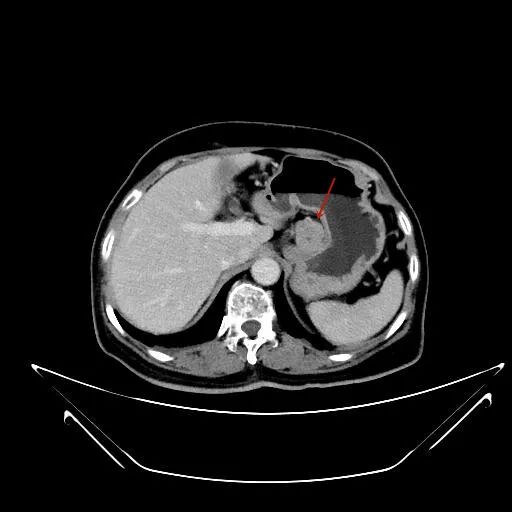

福建省肿瘤医院妇科肿瘤外科与胃肠肿瘤外科协作,一次手术成功完成卵巢与胃的双发肿瘤切除。 术后,患者恢复顺利康复出院。 王女士(化名)今年66岁,2周前因下腹闷痛就诊当地医院,上腹部CT提示: 胃体小弯侧外侧缘肿块,考虑胃外生性间质瘤可能,肿大淋巴结待除; 胃体小弯外侧缘见一类圆形肿块,肿块向外 与胃体壁关系密切,胃左动脉紧贴肿块表面 盆腔磁共振检查提示:盆腔多发囊实性肿物,双侧卵巢肿瘤可能性大(左侧10.9cm×12.3cm,右侧7.3cm×7.4cm)。 子宫双附件区,左右两侧都可见 多房囊实性肿物,子宫受压、前移 面对这一结果,王女士及家属有些不知所措,不知是先处理胃部肿物,还是先处理巨大的盆腔肿瘤。经多方打听后,王女士在家人陪同下,慕名前往福建省肿瘤医院副院长、妇科肿瘤外科孙阳教授门诊。 经过详细询问,孙阳教授了解到,王女士于30年前曾罹患颅脑恶性肿瘤并进行了手术及放疗治疗,这次检查发现的胃部肿块表面紧贴胃左动脉,且合并盆腔巨大肿物,病情复杂,手术风险较大。 在每周例行的妇科肿瘤多学科诊疗(MDT)讨论会上,孙阳教授主持了妇科肿瘤外科、腹部肿瘤外科、影像科、麻醉科及重症医学科等专家,对王女士的病情进行了多学科诊疗(MDT)讨论。专家们认为,王女士胃部的肿物较小,可通过微创(腹腔镜)手术将肿瘤切除;而盆腔肿瘤巨大,在保证肿瘤不播散、无瘤原则的基础上,若要完整彻底切除,则需进行开腹手术。 为了避免患者经历两次手术,减少相关并发症的发生及医疗费用,团队充分评估后决定:妇科肿瘤与胃肠肿瘤外科协作联合开展手术,“一次手术,将两种肿瘤解决”。 手术首先由胃肠肿瘤外科杨春康主任医师行腹腔镜胃小弯侧肿物切除术,在上腹部手术完成后,由妇科肿瘤外科孙阳教授行下腹部的经腹盆腔巨大肿物切除术+全子宫切除术。手术过程顺利,肿瘤被完整切除,术中出血不到100ml。 术后第2天,患者排气并能下地活动,恢复顺利。女子同时查出两种肿瘤不知道该先处理哪个